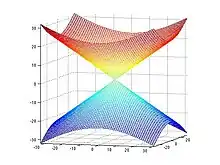

In MRI, the local field induced by non-ferromagnetic biomaterial susceptibility along the main polarization B0 field is the convolution of the volume susceptibility distribution with the dipole kernel : . This spatial convolution can be expressed as a point-wise multiplication in Fourier domain:[6][7] . This Fourier expression provides an efficient way to predict the field perturbation when the susceptibility distribution is known. However, the field to source inverse problem involves division by zero at a pair of cone surfaces at the magic angle with respect to B0 in the Fourier domain. Consequently, susceptibility is underdetermined at the spatial frequencies on the cone surface, which often leads to severe streaking artifacts in the reconstructed QSM.

COSMOS solves the inverse problem by oversampling from multiple orientations.[11][12] COSMOS utilizes the fact that the zero cone surface in the Fourier domain is fixed at the magic angle with respect to the B0 field. Therefore, if an object is rotated with respect to the B0 field, then in the object's frame, the B0 field is rotated and thus the cone. Consequently, data that cannot be calculated due to the cone becomes available at the new orientations.

The underdetermined data in Fourier domain is only at the location of the cone and its immediate vicinity. For this region in k-space, spatial-frequencies of the dipole kernel are set to a predetermined non-zero value for the division. Investigation of more advanced strategies for recovering data in this k-space region is also a topic of ongoing research.[16]